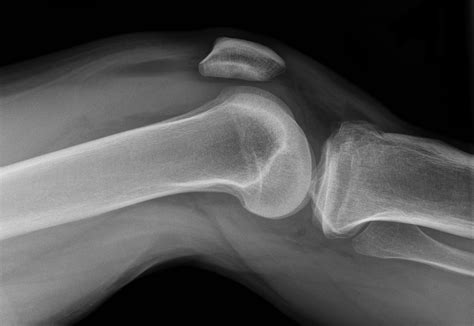

• Imaging Studies: X-rays are often the first step to look for fractures or signs of arthritis. An MRI provides a detailed look at soft tissues like ligaments and menisci, which are invisible on standard X-rays.

• knee joint effusion X-ray